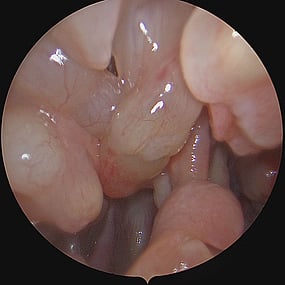

Sinus Pathology

Sino-Nasal Polyps

Sino-Nasal Polyps are non-cancerous growths that develop in the lining of the nose or sinuses. They can obstruct the nasal passages and sinuses, leading to symptoms similar to chronic sinusitis such as nasal congestion, facial pressure, and reduced sense of smell.